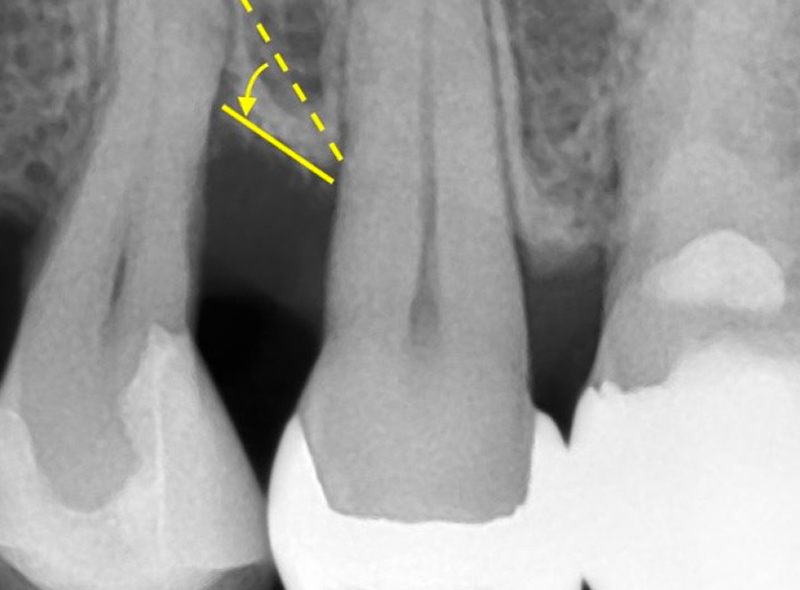

-

02

治療後

治療前の点線の位置から、治療後に実線のラインまで再生されたことを示しています。

| 治療内容 | 重度の歯周病により失われた歯槽骨(歯を支える骨)に対し、歯周組織再生療法(エムドゲインゲル使用)を行い、骨組織の再生を促した。 |

|---|---|

| 治療期間 | 処置約2時間、術後メインテナンス2ヶ月 |

| 費用 | 143,000円(処置88,000円+エムドゲイン薬剤22,000円+骨補填材33,000円) |

| 注意点 |

本治療は外科処置を伴います。 術後、一時的に腫れや痛み、歯がしみる(知覚過敏)などの症状が出ることがあります。 骨の再生量には個人差があり、期待される効果が得られない可能性もあります。 術後の口腔清掃が不十分であったり、定期的なメンテナンスを怠ったりすると、歯周病が再発するリスクがあります。 エムドゲインの特徴として口腔清掃状態が良ければ処置の効果(骨ができる可能性)が約2年続くと言われています。 |